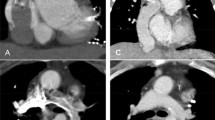

CT images showed a filling defect in the right main pulmonary artery, which was indicative of possible PE (Fig. 1). In addition, inhomogeneous contrast enhancement in the left branch pulmonary artery resulted in incomplete evaluation of possible PE (Fig. 1). The woman subsequently underwent MRI examination for confirmation of possible PE in the bilateral branch pulmonary arteries. The MRI showed completely patent bilateral main pulmonary arteries (Fig. 1). The woman’s symptoms spontaneously resolved within 24 h and she was discharged home.

A 20-year-old woman with a history of tricuspid atresia and right pulmonary artery stenosis who had undergone a lateral Fontan procedure. The woman presented with intermittent chest pain, shortness of breath, and nausea. CTPA was performed for evaluation of possible PE. a Enhanced axial CT image shows a filling defect (arrow) in the right main pulmonary artery and inhomogeneous contrast enhancement (curved arrow) in the left main pulmonary artery. b Enhanced axial MR image demonstrates patent right main (arrow) and left main (curved arrow) pulmonary arteries

CT images demonstrated nonocclusive thrombus in the inferior vena cava portion of the Fontan pathway and PE in the right branch pulmonary artery (Fig. 4). No thrombus or PE was detected in the superior vena cava portion of the Fontan pathway. Upon diagnosis of the thrombus in the Fontan pathway, the child was started on anticoagulation therapy.

A 4-year-old boy with complex congenital heart disease and single-ventricle physiology who had undergone a lateral Fontan procedure. CTPA was performed with simultaneous upper- and lower-limb injections of contrast agent for evaluation of PE after detection of nonocclusive thrombosis in the Fontan pathway with transesophageal echocardiography. a Enhanced axial CT image obtained at the level of the inferior vena cava demonstrates a filling defect (curved arrow) within the Fontan pathway consistent with nonocclusive thrombus. Note the low-density delineating part of the surgical Fontan baffle (straight arrow). b Axial-enhanced CT image at the level of the main pulmonary artery shows a filling defect (arrow) in the right main pulmonary artery (A aorta)